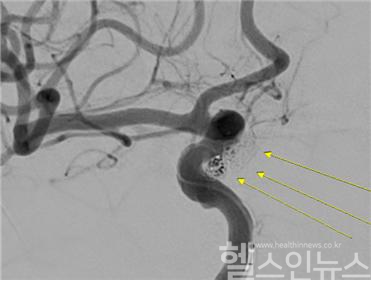

이에 이동혁 센텀종합병원 과장은 곧바로 A 씨에 대해 응급 ‘코일 색전술’을 시행했다. 코일색전술은 개두술(머리를 직접 절개하는 수술) 없이 혈관 내 접근을 통해 뇌동맥류를 치료하는 비침습적 수술법이다. 다리 대퇴부나 팔의 혈관을 통해 미세한 도관(카테터)을 삽입한 후, 이를 뇌혈관에 위치시키고 동맥류 내부에 특수 금속 코일을 채우는 것이다. 이 수술법은 혈류 흐름을 차단해 추가 출혈을 예방할 뿐만 아니라 미세 침습 수술이라 회복 속도가 빠르고, 필요할 경우 추가적인 색전술을 시행할 수 있는 장점이 있다.